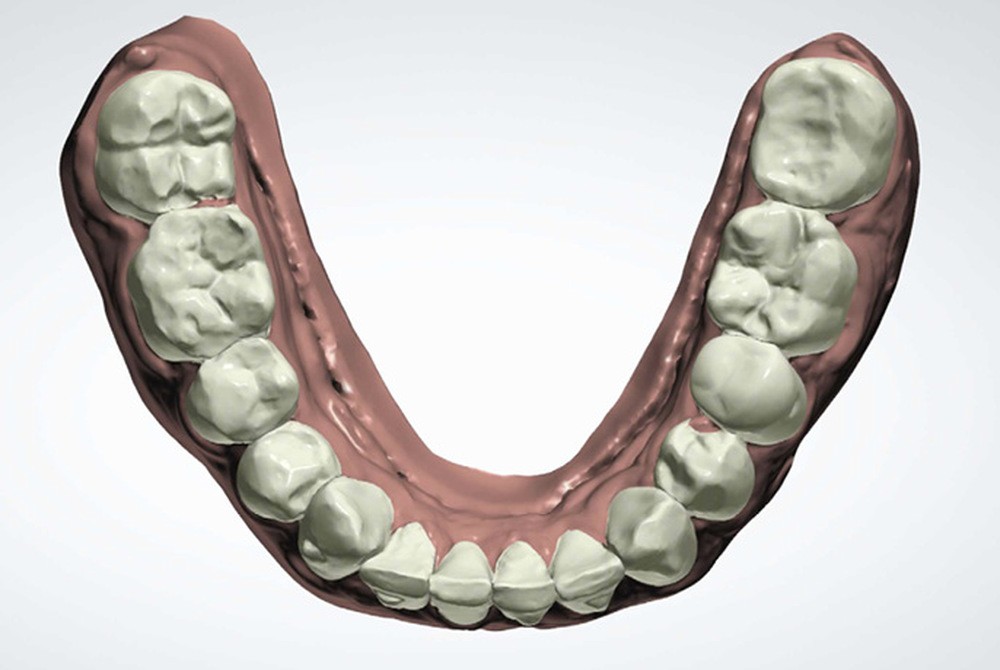

Présentation du cas clinique (fig. 1 à 3)

Le patient, âgé de 58 ans, présente un encombrement dentaire mandibulaire de 5 mm dans un contexte squelettique hypodivergent.

Plan de traitement

(fig. 4 à 10)

Le plan de traitement établi conjointement avec son chirurgien-dentiste traitant consiste à réaliser un alignement dentaire mandibulaire et à réaliser des extractions de 16 et 15 pour un remplacement par prothèse implanto-portée.

La durée orthodontique prévue est de neuf mois, avec comme contrainte principale l’absence de possibilités de modification des formes d’arcades.

Le gain de place se fera par des réductions interproximales sur la zone incisivo-canine mandibulaire.